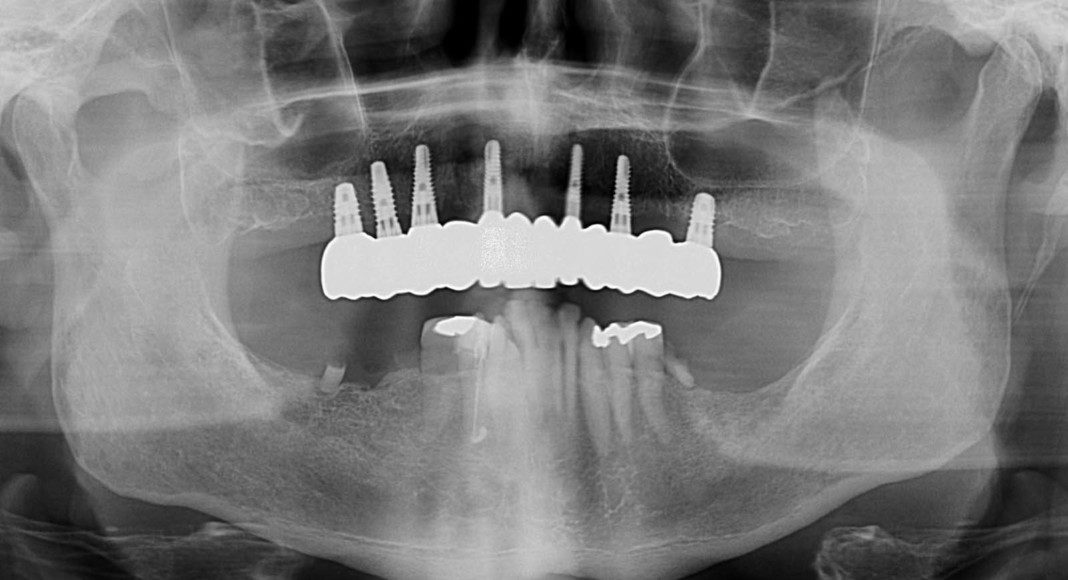

Day of surgery panoramic x-ray. Test implants were placed and adequate insertion torque was obtained (bone density and implant stability measured ≥ 25 Newton-centimeters) which qualifies multiple implants for immediate temporaries. All other teeth were extracted and a total of eight implants placed in the upper jaw (maxilla).